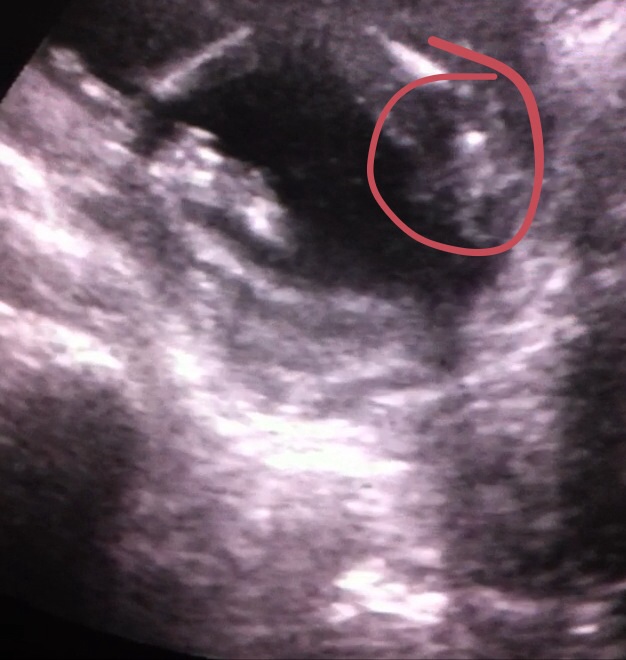

Maybe a boy

Maybe boy or swollen labia? Not sure

1st 2 pics were from 16 weeks scan everyone was unsure of those. ***NEW 3 pictures from 17 weeks scan

The first two images look like a boy. Congrats!

Thinking girl.

looks boyish on all of them.

Boy